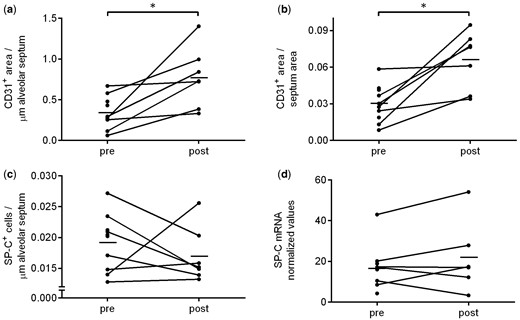

2.免疫組織化學(xué)分析

LVRS+BM-MSC輸注后,肺泡隔內(nèi)的CD31?+?(內(nèi)皮細(xì)胞)面積增加了3倍(P=0.016),已根據(jù)肺泡隔長(zhǎng)度和總肺泡面積進(jìn)行校正(圖3a和b)。歷史對(duì)照的肺泡隔中CD31表達(dá)沒(méi)有顯著變化。SP-C(肺泡II型細(xì)胞)未見(jiàn)變化(圖3c)。

LVRS+BM-MSC輸注后,肺泡隔中CD3+T細(xì)胞的數(shù)量明顯高于之前 (?P=0.016) (圖4a )。

除一名患者外,所有患者在LVRS+BM-MSC輸注后,肺泡隔中CD4+?T細(xì)胞的數(shù)量均有所增加( P=0.30;按倍數(shù)變化計(jì)算P=0.047) (圖4b)